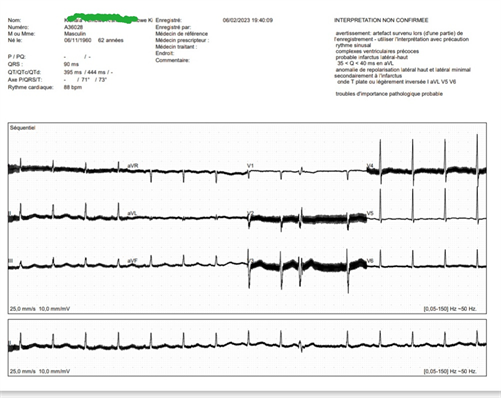

The electrocardiogram found left ventricular hypertrophy, incomplete right bundle branch block and apical ischemia (see Figure 1).

Figure 1. Standard ECG showing left ventricular hypertrophy, incomplete right bundle branch block and apical ischemia.